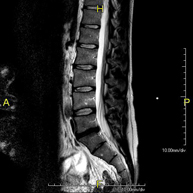

Prova diagnòstica no invasiva que consisteix en l'obtenció d'imatges d'alta definició anatòmica de la columna dorsal mitjançant l'ús d'un camp electromagnètic i ones de ràdio (com un emissor i un receptor). No utilitza radiació ionitzant. Indicacions: traumatisme, problemes degeneratius, hèrnies, tumors. - RM de Columna lumbar

Prova diagnòstica no invasiva que consisteix en l'obtenció d'imatges d'alta definició anatòmica de la columna lumbar i sacre mitjançant l'ús d'un camp electromagnètic i ones de ràdio (amb un emissor i un receptor). No utilitza radiació ionitzant. Indicacions: traumatismes, ciàtica, hèrnies discals, tumors, infeccions - RM Mielografia

Prova diagnòstica no invasiva que consisteix en l'obtenció d'imatges d'alta definició anatòmica de la columna dorsal, mitjançant l'ús d'un camp electromagnètic i ones de ràdio (amb un emissor i un receptor). No utilitza radiació ionitzant. Indicacions: traumatisme, problemes degeneratius, hèrnies i tumors. - RM Columna Lumbar

Prova diagnòstica no invasiva que consisteix en l'obtenció d'imatges d'alta definició anatòmica de la columna lumbar i sacre mitjançant l'ús d'un camp electromagnètic i ones de ràdio (amb un emissor i un receptor). No utilitza radiació ionitzant. Indicacions: traumatismes, ciàtica, hèrnies discals, tumors i infeccions. - RM de Sacre-còccix